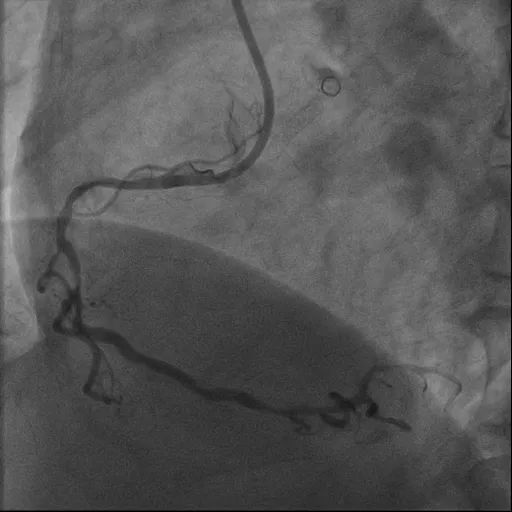

造影检查显示:冠状动脉三支病变。其中,右冠状动脉近中段狭窄钙化最重处约 90%,伴重度弯曲;左冠状动脉前降支近中段狭窄钙化最重处约 85%;左冠状动脉回旋支近段狭窄约 85%。

术中,充分预处理 Shockwave 球囊后,沿导丝推送球囊至钙化病变血管段,扩张球囊后,释放冲击波。经多次单轮操作,逐一击碎「坚如磐石」的钙化病变,成功置入支架。

造影可见血管狭窄明显缓解,管腔面积得到有效恢复,血流通畅。